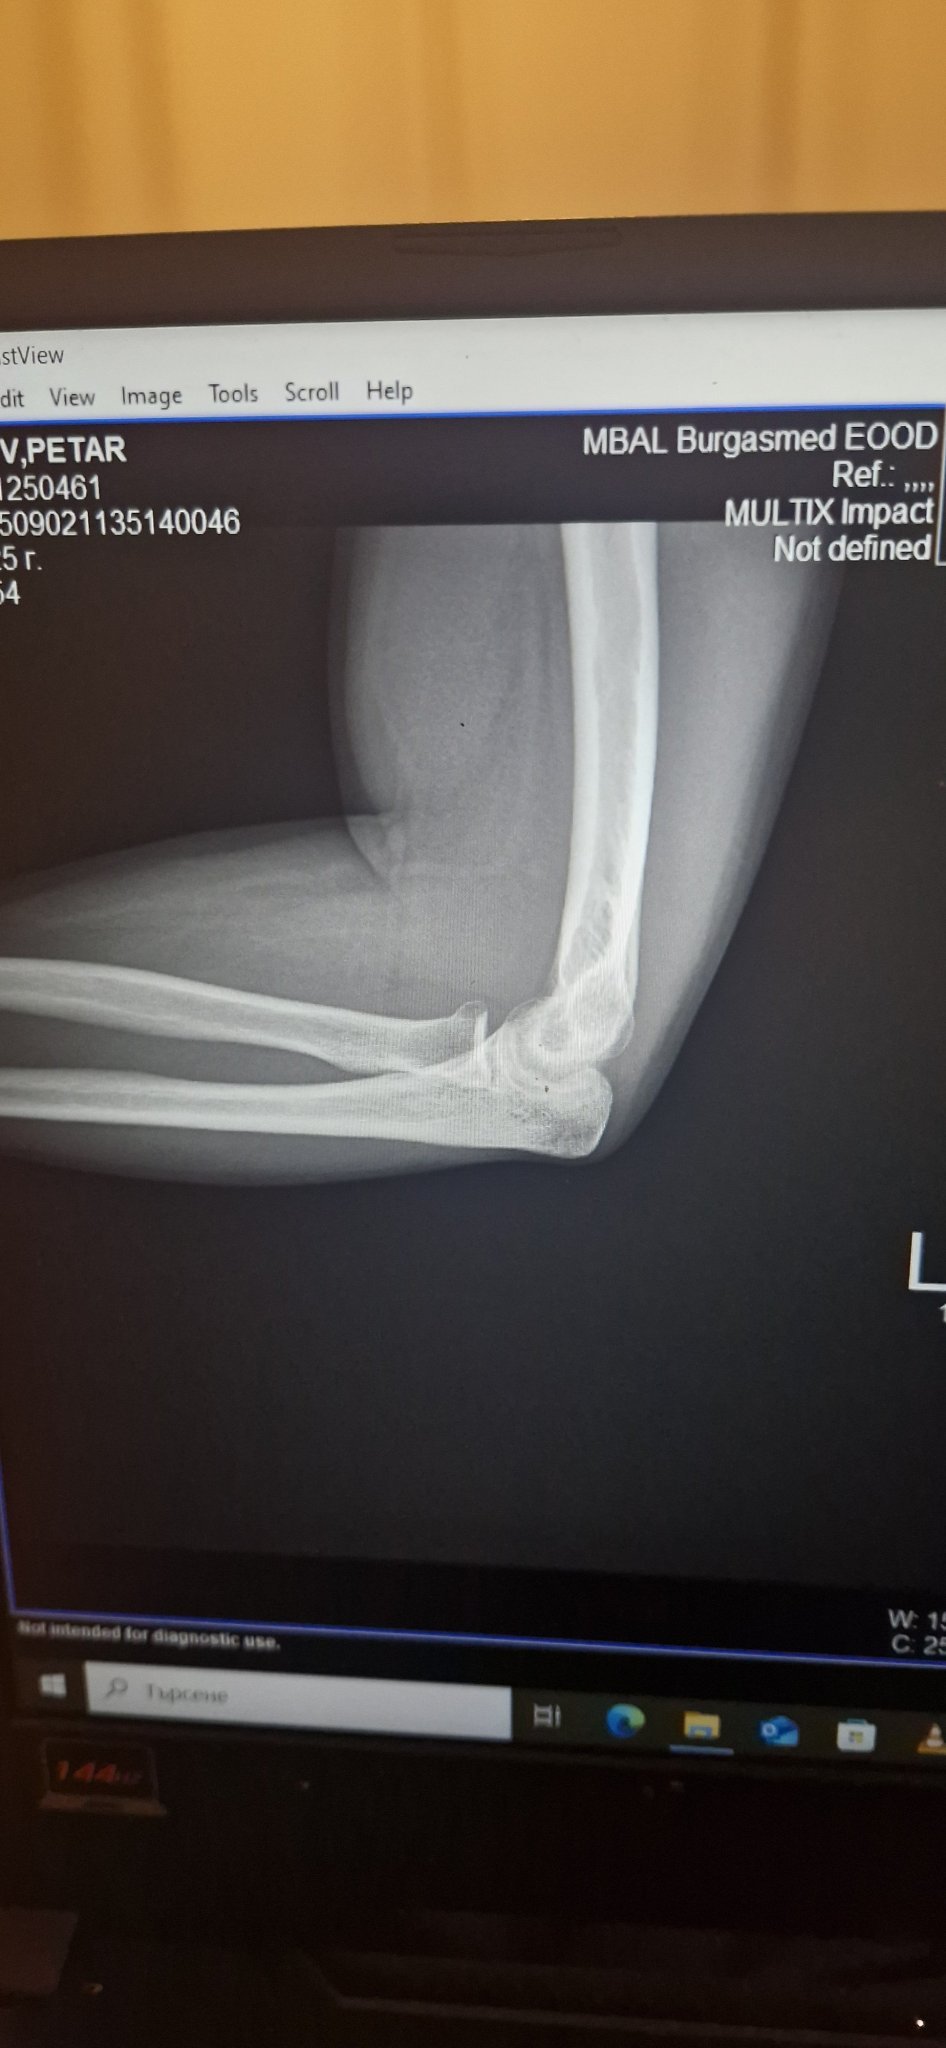

докторе бих те ли споделили виждате ли нещо нередно на ренгена на лакътя

Здравейте, благодаря за въпроса.

За жалост, така качена, снимката е с лошо качество и не мога да кажа с точност.

Много в важен и клиничният преглед.